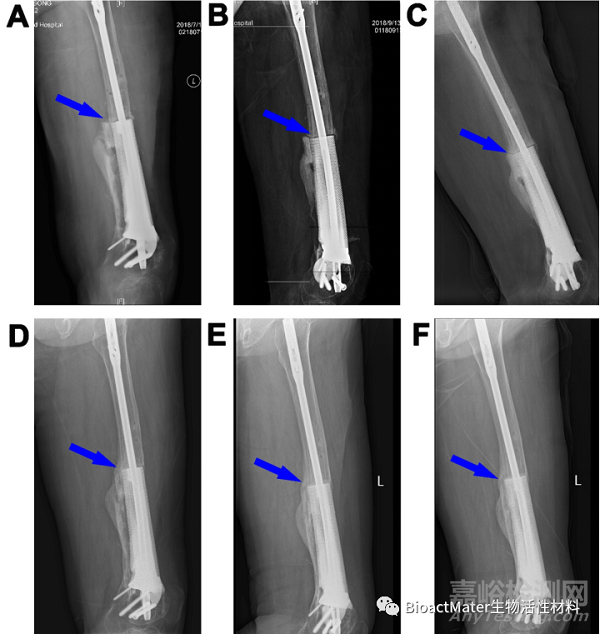

圖5.3D打印多孔Ti6Al4V內(nèi)植物重建股骨缺損(病例2)。末次術(shù)后即刻(A)和植入后2(B)、5個(gè)月(C)、8個(gè)月(D)、14個(gè)月(E)和20個(gè)月(F)重建的11cm股骨缺損的X線圖像。藍(lán)色箭頭表示內(nèi)植物和宿主骨之間的骨整合。